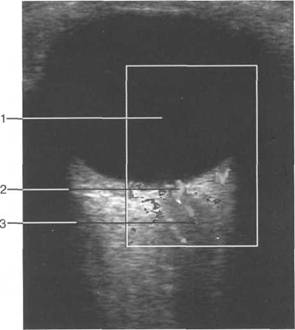

При сонографии отчетлив 121h711b о выявляется чивается хрусталиком, а сбоку - ресничным

четлив 121h711b о дифференцировать зрительный нерв и глазодвигательные мышцы (рис. 2.16, 2.17).